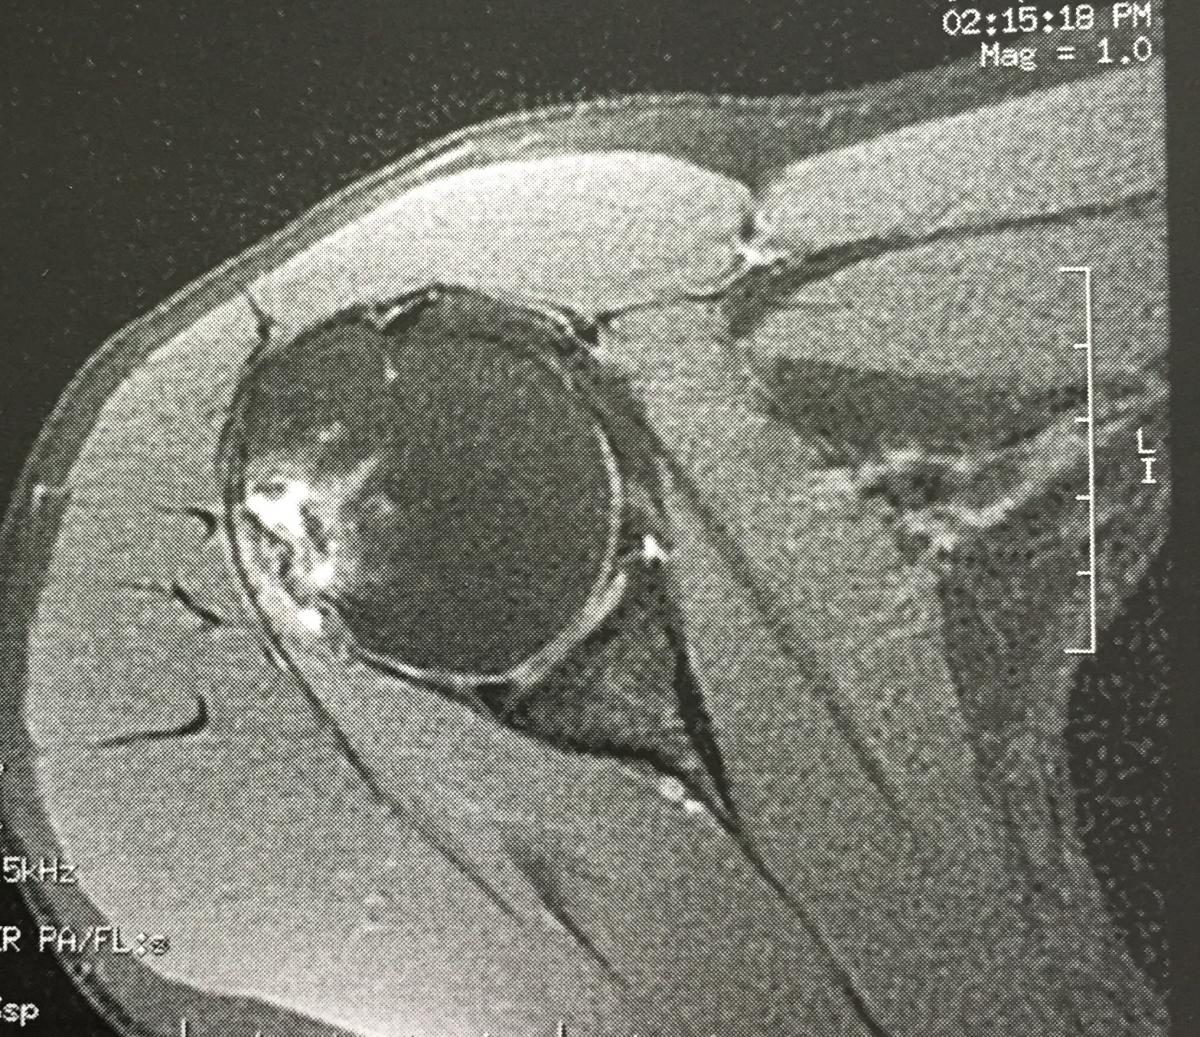

image.jpeg

Tja Leute, es gibt nicht so tolle Neuigkeiten was meine Schulterschmerzen betrifft. Neben einem Einriss einer Gelenkkapsel/Lippe zeigt sich auf dem MRT eine chronische Entzündung einer Sehne und leider auch eine Durchblutungsstörung des Gelenkkopfes. Ich habe mal ein bisschen gegoogelt und Bilder verglichen und bereite mich seelisch-moralisch auf eine längere TT Pause vor. Der Orthopäde muss das alles noch genau ansehen. Die Wahrscheinlichkeit ist IMHO aber da, dass es sich u.U. um eine Humeruskopfnekrose handelt ( Stadium ? ), was mit einer OP behandelt werden muss. Ob es soweit kommt dass ich mit einer (Teil-)Gelenkkopfprothese versorgt werden muss, wird sich in den nächsten 1-2 Wochen vermutlich zeigen. Habe bei zwei Ärzten bestätigte Termine und werde auf alles gefasst sein. Bis in den Mai will/muss ich aber noch durchhalten und danach wird man dann sehen. :yesbad:

Also so super toll fühle ich mich damit natürlich nicht... Aber wenn es so ist, dann soll es so sein und ich werde mir eine böse Titanprothese aussuchen, speziell für Moderene Verteidigung !